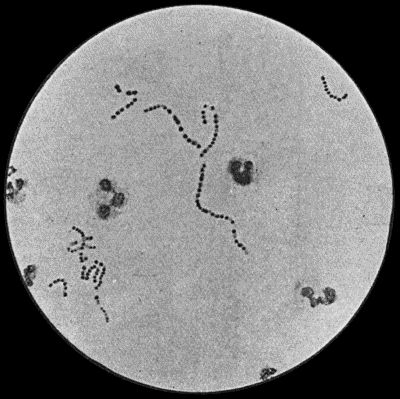

| 2. | Staphylococcus aureus in Pus from case of Osteomyelitis | 25 |

Cocci or micrococci are minute round bodies, averaging about 1 µ in diameter. The great majority are non-motile. They multiply by fission; and when they divide in such a way that the resulting cells remain in pairs, are called diplococci, of which the bacteria of gonorrhœa and pneumonia are examples (Fig. 5). When they divide irregularly, and form grape-like bunches, they are known as staphylococci, and to this variety the commonest pyogenic or pus-forming organisms belong (Fig. 2). When division takes place only in one axis, so that long chains are formed, the term streptococcus is applied (Fig. 3). Streptococci are met with in erysipelas and various other inflammatory and suppurative processes of a spreading character.

It is found that the staphylococci, which cluster into groups, tend to produce localised lesions; while the chain-forms—streptococci—give rise to diffuse, spreading conditions. Many varieties of pyogenic bacteria have now been differentiated, the best known being the staphylococcus aureus, the streptococcus, and the bacillus coli communis.

Staphylococcus Aureus.—This is the commonest organism found in localised inflammatory and suppurative conditions. It varies greatly in its virulence, and is found in such widely different conditions as skin pustules, boils, carbuncles, and some acute inflammations of bone. As seen by the microscope it occurs in grape-like clusters, fission of the individual cells taking place irregularly (Fig. 2). When grown in artificial media, the colonies assume an orange-yellow colour—hence the name aureus. It is of high vitality and resists more prolonged exposure to high temperatures than most non-sporing bacteria. It is capable of lying latent in the tissues for long periods, for example, in the marrow of long bones, and of again becoming active and causing a fresh outbreak of suppuration. This organism is widely distributed: it is found on the skin, in the mouth, and in other situations in the body, and as it is present in the dust of the air and on all objects upon which dust has settled, it is a continual source of infection unless means are taken to exclude it from wounds.